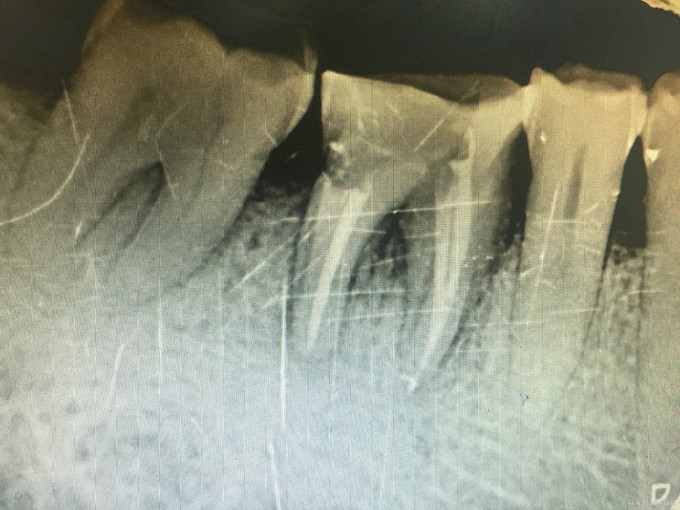

临床检查:46牙合面无明显龋坏,远中邻面食物嵌塞探疼(+),冷(++),叩(-),松动度(-),牙周红肿。 辅助检查:X线示46远中邻面龋坏累积髓腔,根尖周牙周膜增宽。

诊断:46牙髓炎 治疗:经患者知情同意后,46局麻去腐降牙合,开髓拔髓寻找根管口,建立直线通路,扩通根管,确定工作长度。S3/EDTA凝胶镍钛器械,低浓度次氯酸钠冲洗根管,预备至25/06,氢氧化钙诊间封药,一周后复诊,试主尖X线示恰充,试干根管,导AH-PLUS糊剂,VDW热压胶垂直加压根充,术后见根管恰充,暂封调合抛光。桩冠修复。